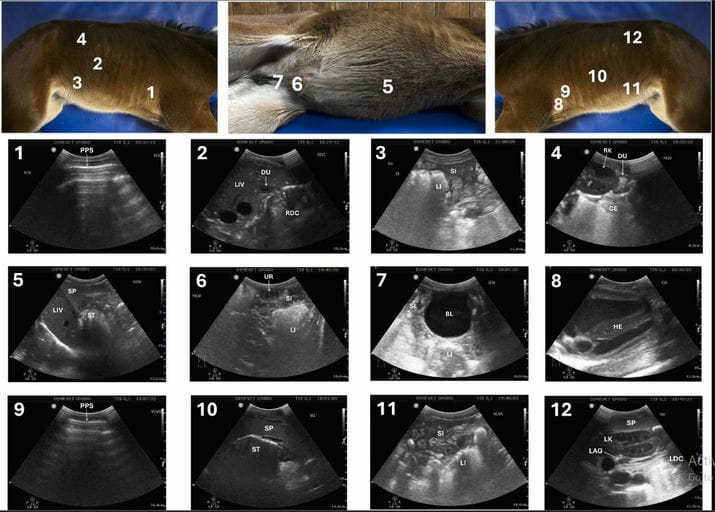

Client-owned foals younger than 30 days admitted during the 2024 foaling season were prospectively enrolled. Seventeen healthy and 23 sick foals underwent a 12-window thoraco-abdominal Focused Ultrasound (FUS) protocol performed by a clinician with limited ultrasound experience after brief training. The protocol included four right-sided, three ventral, and five left-sided acoustic windows. Feasibility and organ visualization were assessed in healthy foals, while diagnostic usefulness in sick foals was evaluated retrospectively by comparing FUS findings with final diagnoses. Based on results, a shortened 7-window Foal Oriented Compressed Ultrasound (FOCUS) protocol was developed and tested in six additional foals by three clinicians with varying levels of experience to assess examination time and practicality.

The 12-window FUS protocol. Probe placement site (top) and corresponding ultrasound image in a healthy foal (bottom) for the 12 acoustic windows of the FUS protocol. Four windows on the right side: 1. Right cranio-ventral thoracic window - Pleuropulmonary surface (PPS); 2. Hepato-duodeno-colic window - Liver (LI), right dorsal colon (RDC) and duodenum (DU); 3. Ventro-lateral abdomen window - Small intestine (SI) and large intestine (LI); 4. Nephro-cecum-duodenal window - Cranial pole of the right kidney (RK), cecum (CE) and duodenum (DU). Three windows on the ventral abdomen: 5. Retro-sternal window - Liver (LI), spleen (SP) and stomach (ST); 6. Meso-gastric window - Umbilical remnants (UR), small intestine (SI) and large intestine (LI). 7. Hypo-gastric window - Bladder (BL), small intestine (SI) and large intestine (LI). Five windows on the left side: 8. Cardiac window - Heart (HE); 9. Left cranio-ventral thoracic window - Pleuropulmonary surface (PPS); 10. Spleno-gastric window - Spleen (SP) and stomach (ST); 11. Ventro-lateral abdomen window - Small intestine (SI) and large intestine (LI); 12. Nephro-splenic window - Spleen (SP), left kidney (LK), left dorsal colon (LDC) and left adrenal gland (LAG).